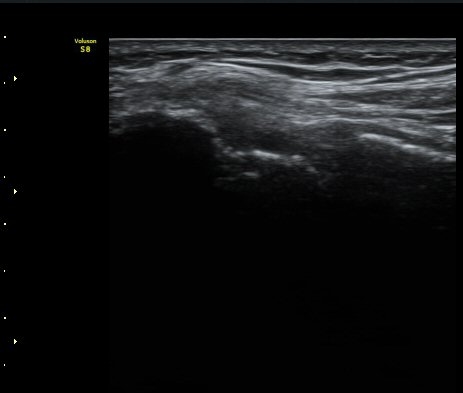

ÃÊÀ½ÆÄ °Ë»ç

³»»ó°ú Á¾´Ü¸é°Ë»ç»ó  ³»ÃøºÎÀδë Àú¿¡ÄÚ ºÎÁ¾°ú ³»»ó°ú ÀÎ´ë ºÎÂøºÎ ÇÇÁú°ñÀÇ ºÒ±ÔÄ¢º¯È­¿Í

°ñÆíÀÌ °üÂûµÇ°í(±×¸² 1, 2, 3, 4) ÀÌ·±¼Ò°ßÀº °ÇÃø°ú ºñ±³ÇÏ¸é ´õ¿í ¶Ñ·ÈÇÔ(±×¸² 5, 6).